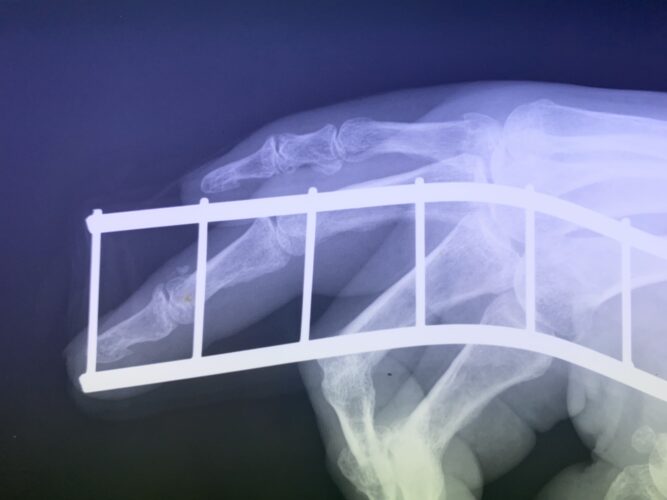

骨折・脱臼に関する研修会の役員をしています。同じ役員の先生方と講師のもと、同業の先生達に向けて骨折・脱臼の治し方の実技指導をしております。

さわやか千葉県民プラザ(指骨骨折)